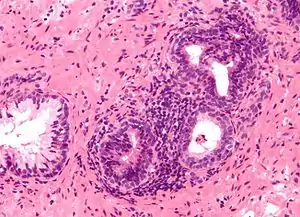

The term prostatitis refers to inflammation of the tissue of the prostate gland. It may occur as an appropriate physiological response to an infection, or it may occur in the absence of infection.[5]

The conditions are distinguished by the different presentation of pain, white blood cells (WBCs) in the urine, duration of symptoms and bacteria cultured from the urine. To help express prostatic secretions that may contain WBCs and bacteria, prostate massage is sometimes used.[11]